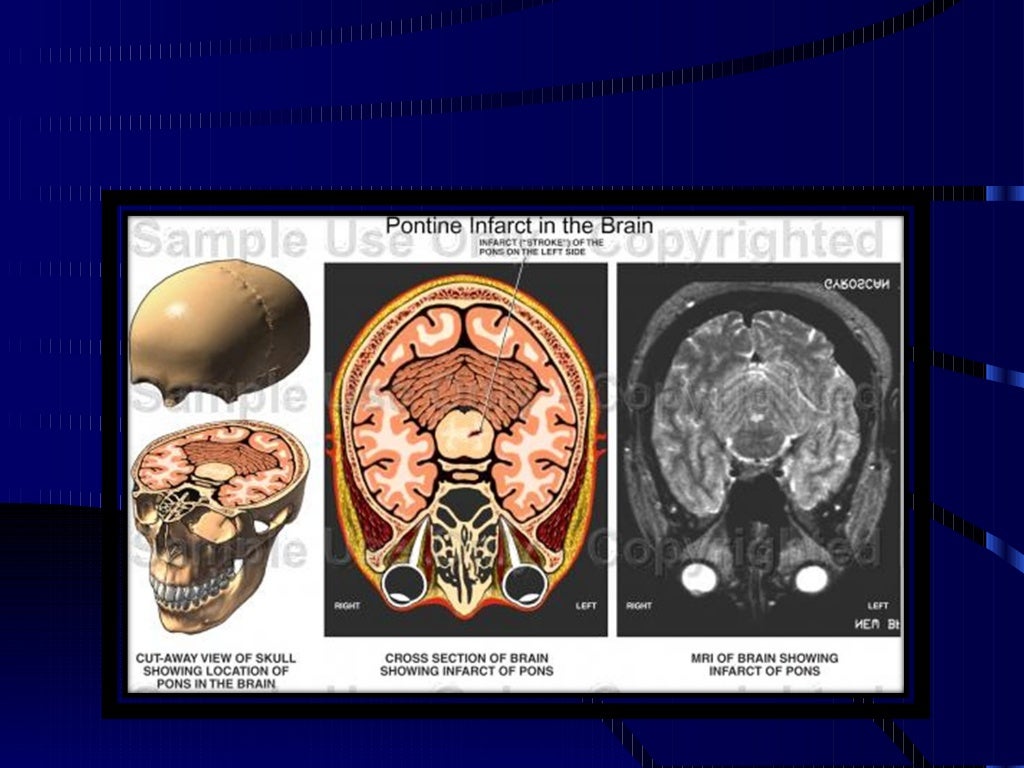

1.- Síndrome motor puro: Es un cuadro caracterizado por paresia de grado variable, facio braqui crural armónica, sin alteraciones sensitivas. Se describe que este sería el más frecuente de todos los síndromes lacunares. Éste estaría dado por lesión del brazo posterior de la cápsula interna (irrigada por la arteria coroidea anterior, rama de la carótida interna, previo a su bifurcación), centro oval o en caso de que no exista compromiso facial, por lesiones en protuberancia (lesión de arterias penetrantes protuberanciales, ramas de la arteria basilar)

4.- Síndrome ataxia hemiparesia: Cuadro caracterizado por una paresia de grado variable, disarmónico, de predominio crural y gran ataxia en zona braquial ipsilateral. La lesión suele encontrarse en pie protuberancial (irrigado por ramas penetrantes de la arteria basilar). Otras localizaciones son a nivel del centro oval o en corona radiada.